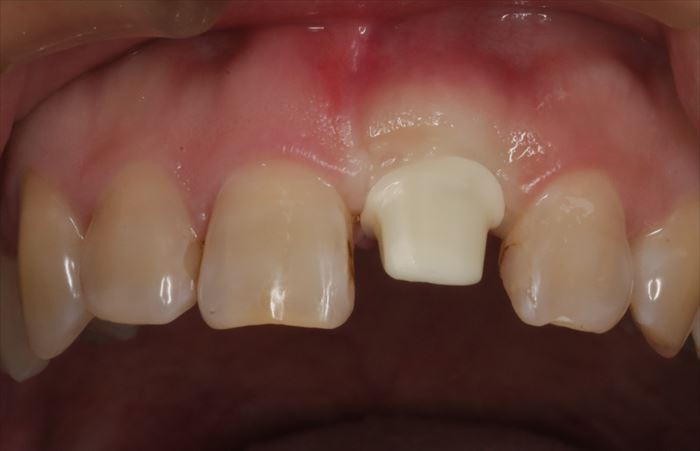

ヒーリングキャップを外しました。

歯肉はヒーリングキャップに沿って治癒しています。

隣接歯の むし歯と古いコンポジットレジンは次回治療します。

本日は、慣れと咬み合わせの確認のため、プラスチック製の仮歯をセットします。